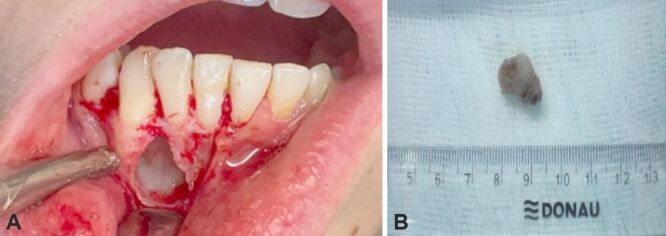

平堡瘤是一种钙化上皮性牙源性肿瘤,可能是由于牙齿薄层残留物的发育障碍引起的。这种肿瘤主要影响生命中第三个十年的人,女性发病较晚。该肿瘤有两种形式,即骨内(中央型)和骨外(周围型),前者的术后复发率较高,约为 14%。尽管这种肿瘤很罕见,但由于其症状类似牙科问题和头痛,甚至可能没有症状,因此可能会被误诊。在放射学上,它表现为放射线透明区和放射线不透明区的混合,有时为单眼或多眼。组织病理学上,它的特征是多角形上皮细胞的巢状和片状,胞质嗜酸性,核仁突出。嗜酸性淀粉样物质和钙化是该病的显著特征,从小凝块到较大的聚集体都有。淀粉样蛋白的确切来源尚不清楚,但认为它们来自降解的角蛋白丝。治疗方法因肿瘤位置而异,由于颌骨肿瘤具有侵袭性生长和对周围组织的侵袭,因此需要进行包括骨切除在内的侵入性手术。准确的个体化治疗对患者的预后至关重要,尤其是在肿瘤钙化缺失的情况下,预示着对健康的严重影响。我们的研究包括一例 12 岁患者的病例报告,该患者到牙科诊所就诊时主诉右下门牙部位零星疼痛。在对该区域进行临床检查时,我们发现牙槽骨变形,粘膜凹陷。我们按照放射学检查、病灶切除和组织病理学检查的时间顺序进行了检查,以获得明确诊断。

Pindborg tumor is a calcifying epithelial odontogenic tumor possibly arising from developmental disturbances in dental lamina remnants. It predominantly affects individuals in their third decade of life, with women also experiencing later onset. The tumor exists in two forms, namely intraosseous (central) and extraosseous (peripheral), with the former showing higher post-surgery recurrence rates of about 14%. Despite its rarity, the tumor can be misdiagnosed due to symptoms resembling dental issues and headaches, or it may even be asymptomatic. Radiologically, it presents a mix of radiolucent and radiopaque areas, sometimes unilocular or multilocular. Histopathologically, it is characterized by nests and sheets of polygonal epithelial cells with eosinophilic cytoplasm and prominent nucleoli. The presence of eosinophilic amyloid-like material and calcifications is distinctive, ranging from small concretions to larger aggregates. The exact origin of amyloids is unknown, but they are thought to derive from degraded keratin filaments. Treatment varies by tumor location, with more invasive procedures required for jaw tumors, including bone resection, due to their aggressive growth and invasion of the surrounding tissues. Accurate, individualized treatment is crucial for patient outcomes, particularly in cases where the tumor's calcification is absent, indicating a severe impact on health. Our study included a case report of a 12-year-old patient who presented to the dental clinic complaining of sporadic pain in the area of the lower right front teeth. During a clinical examination of the area, we noticed a deformation of the alveolar bone, with a depressed mucosa. We followed the chronological steps of radiological examination, lesion excision, and histopathological examination to obtain a definitive diagnosis.